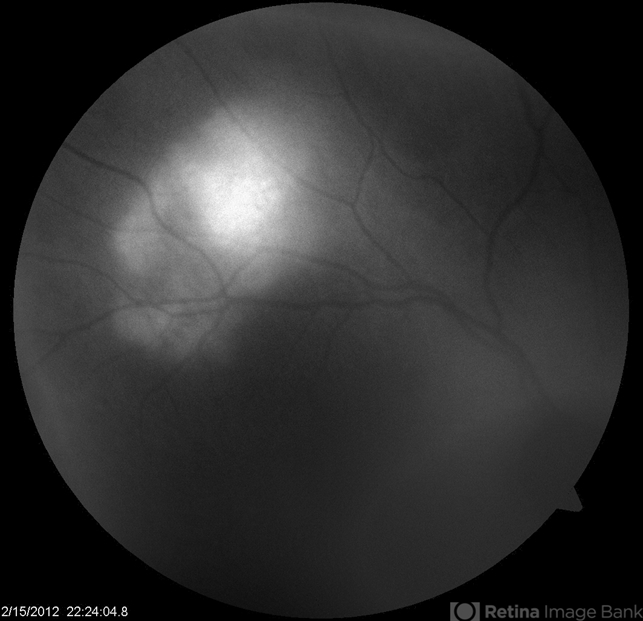

- idiopathic sclerochoroidal calcification

- Kristin Konecki, OcuSight Eye Care Center, Rochester, NY

- Fundus camera

- AF